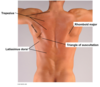

Trapezius

Origin : back of the skull, nuchal ligament, and spinous processes of C7 to T12 vertebrae.

Insertion : lateral third of clavicle, acromion and spine of the scapula.

Innervation : accessory nerve

Blood Supply : superficial branch of the transverse cervical artery

Action : elevation, retraction, and depression of the scapulae. The upper and lower parts working together, elevate the glenoid cavity superiorly.

Latissimus dorsi

Origin : spinous processes of thoracic vertebrae below T6, thoracolumbar fascia, iliac crest and lower 3 or 4 ribs.

Insertion : intertubercular groove of the humerus.

Innervation : thoracodorsal nerve

Action : extends, adducts and medially rotates the upper extremity

Triangle of auscultation

Triangle of auscultation formed by the trapezius, rhomboid major and latissimus dorsi.